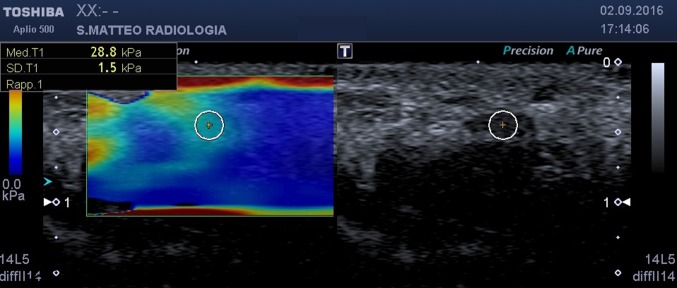

Fig. 2.

SWE, axial scan at carpal tunnel inlet. On the left the b-mode image, on the right the elastogram. The circular ROI encloses the median nerve

at the carpal tunnel inlet (scaphoid–pisiform level) (Fig. 2);

Using this approach, the values of the stiffness of the nerve at the various sampling points were obtained (Figs. 1, 2, 3). Statistical analysis was performed using MedCalc (MedCalc Software, Ostend, Belgium).